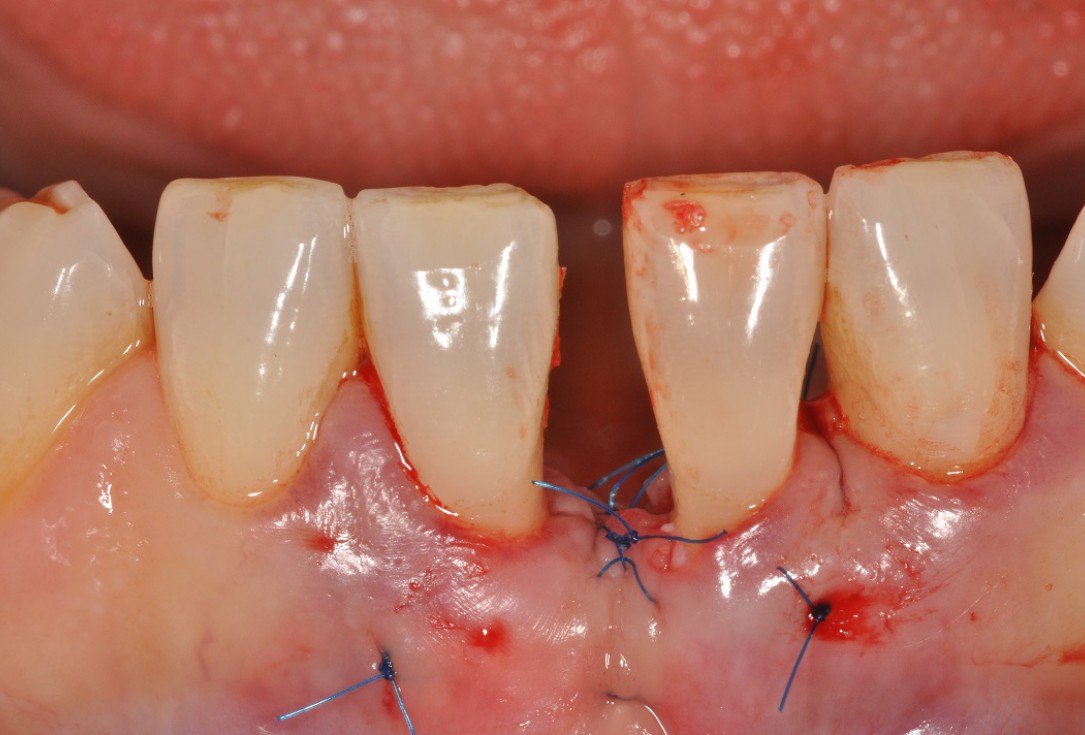

07/13 - Suturing.

Wide intrabony defect treated with the modified papilla preservation flap in conjunction with Straumann® Emdogain® and autogenous bone - Dr. B. Molnar